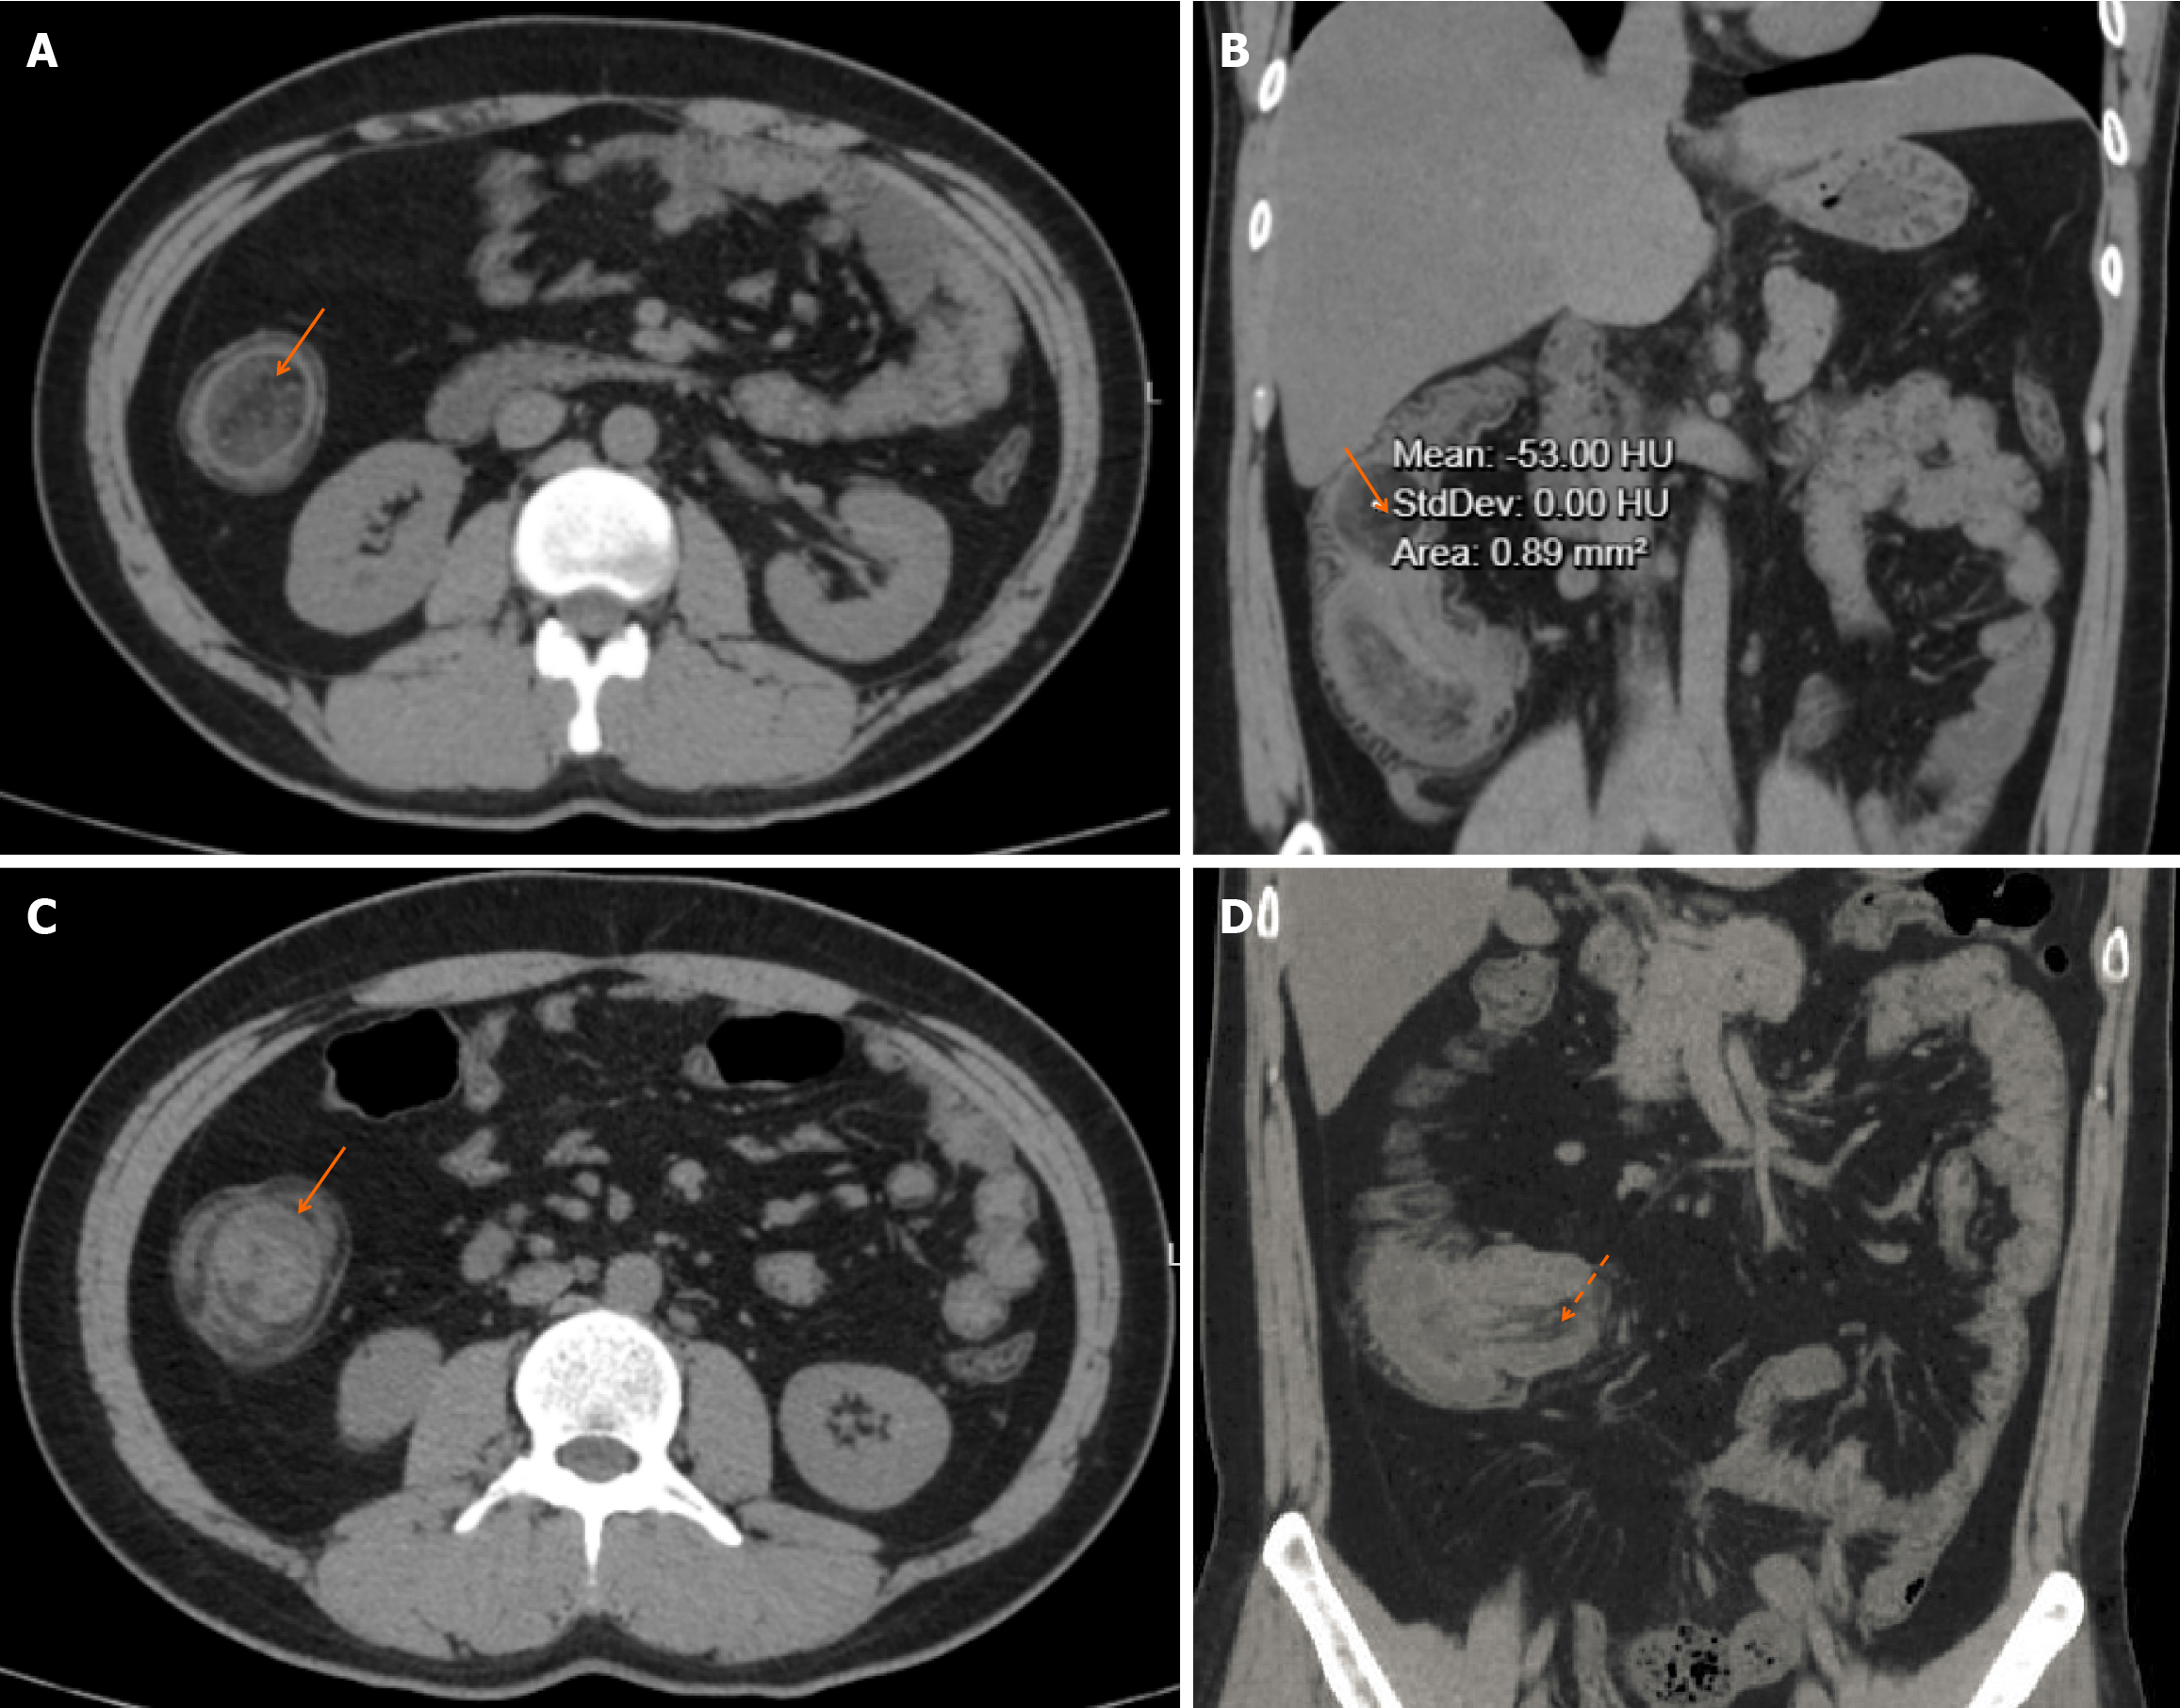

Figure 1 Abdominal computed tomography.

A and B: Axial and coronal computed tomography (CT) images showing a well-circumscribed, oval-shaped mass (arrow) with homogeneous fat attenuation (approximately -53 Hounsfield units) within the ascending colon, pathognomonic for a lipoma, acting as the lead point for the intussusception; C: Axial CT image demonstrating the “target sign” (arrow), formed by the concentric rings of the edematous intussusceptum within the intussuscipiens; D: Coronal CT image showing the elongated intussuscepted bowel loop, known as the “sausage sign” (dashed arrow). HU: Hounsfield units.